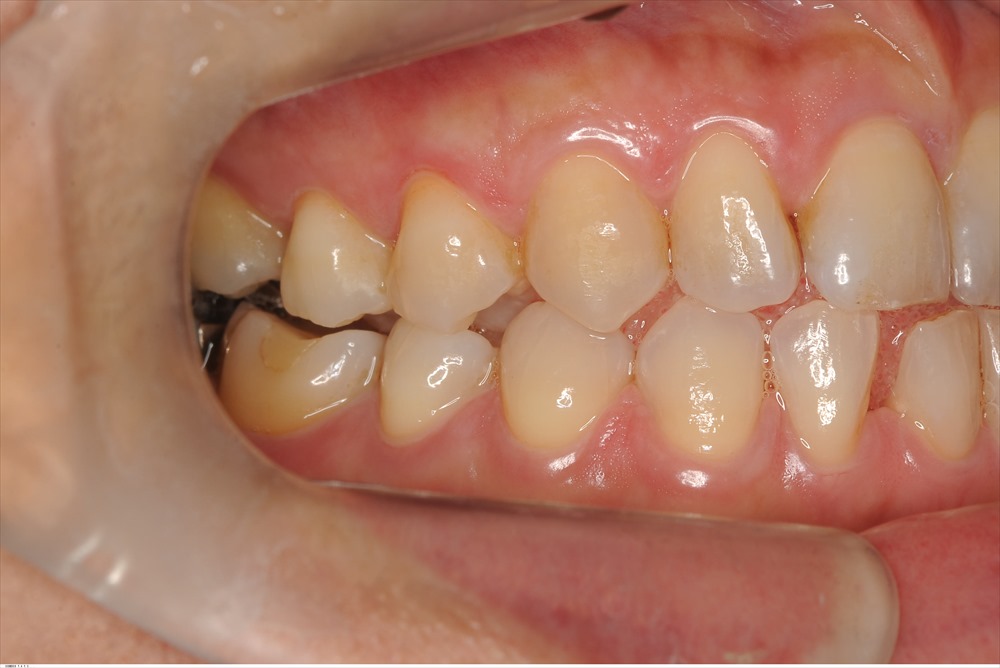

40代女性

右下6番の歯周病です。

今にも抜けそうな状態でしたが